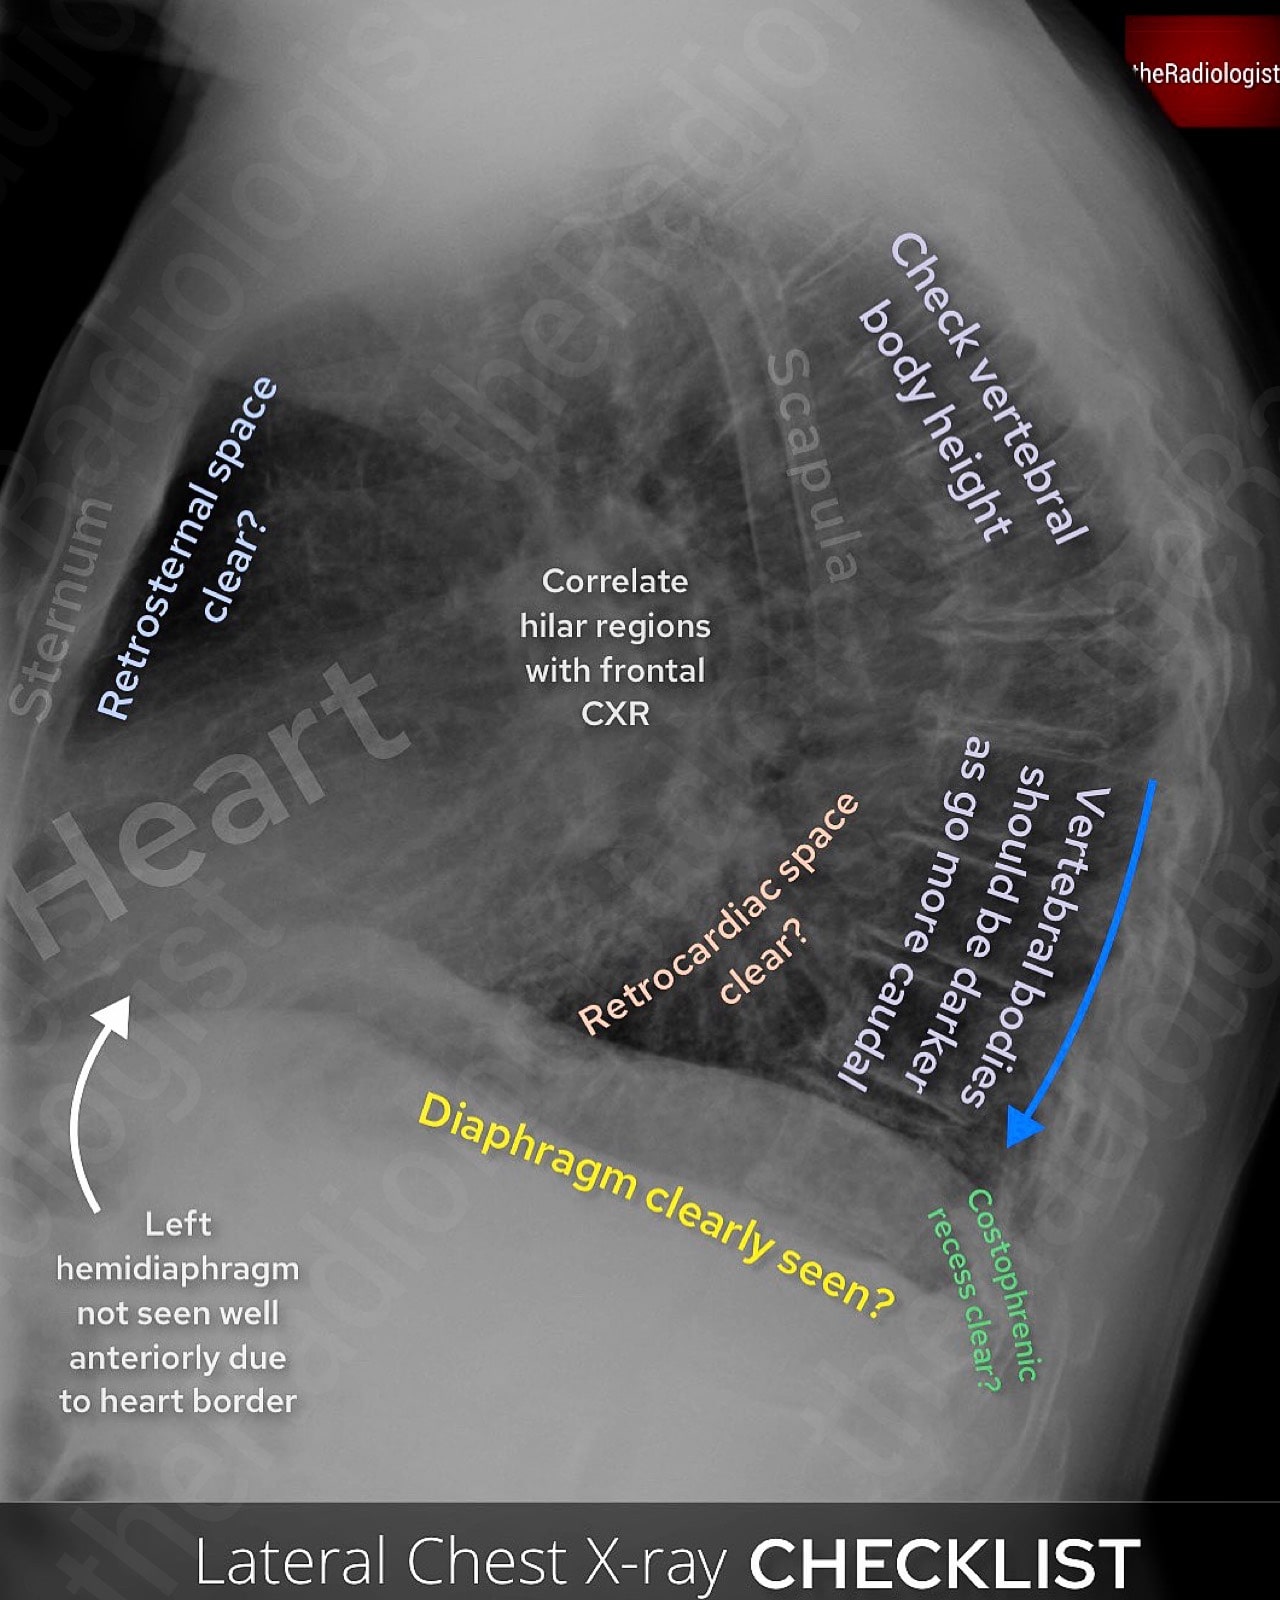

Lateral chest X-Ray review

Now let’s move on to the lateral chest X-Ray.

The lateral chest X-ray isn’t performed routinely in most UK centres, but it is in many places around the world as it can be extremely useful. It highlights blind spots that the frontal view doesn’t show well, so it’s worth having a systematic approach when reviewing one.

Review areas on a lateral chest X-Ray.

1. Retrosternal and retrocardiac space

Start by assessing the sternum for fractures or lesions. Then look at the space directly behind it, which should appear as a clear area of lucent lung. If that lucency is lost, consider an anterior mediastinal mass. Behind the heart, carefully check for any opacity that may not be visible on the frontal view.

2. Vertebral bodies

The lateral film provides a much better view of the vertebral bodies than the frontal. Look for loss of vertebral height or endplate disruption.

Normally, the vertebrae should appear progressively darker as you move caudally; if they look whiter towards the base, this could indicate lower lobe consolidation or an underlying mass.

3. Diaphragm and lung bases

Both hemidiaphragms should be visible and clearly defined, although remember the anterior left hemidiaphragm is partially obscured by the heart. Look for any loss of definition due to collapse, consolidation, or effusion. The posterior costophrenic recesses should also be checked carefully for pleural fluid.

4. Hilar regions

If the hilum looks unusually dense on the frontal view, the lateral can help determine whether the abnormality is situated anteriorly or posteriorly.

5. Middle lobe

Middle lobe collapse is easily overlooked on the frontal view but more readily seen on the lateral. Look for a wedge-shaped opacity projected over the cardiac silhouette.